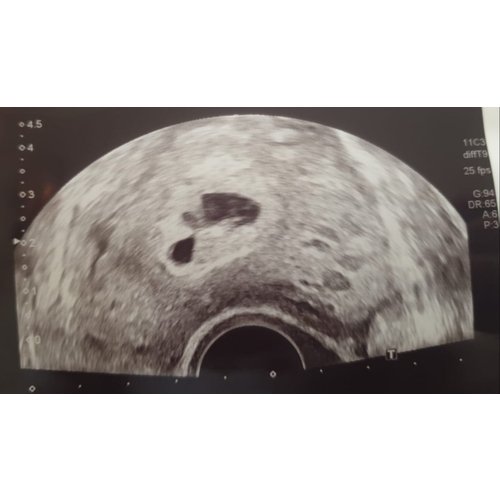

Hey, is er iemand die dit nog meer heeft gehad? Ik heb namelijk vandaag een soortgelijke echo gehad en begreep er niet veel van.